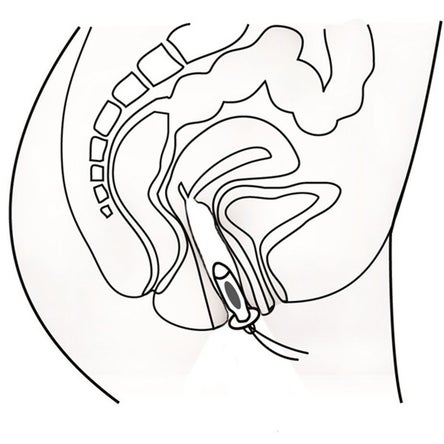

Sanfte Therapie gegen Inkontinenz mit dem Inkontinenz-Therapiegerät IT-6

- Es dient zur Vorbeugung bzw. Verringerung von Blasenschwäche

- Behandlung von Inkontinenz nach einer Geburt (Tibialis-Stimulation am Bein, des unteren Rückenbereiches oder des gesamten Unterleibes)

- Trainieren der Schliessmuskeln zur Behandlung von Stress-/ Drang-/ Misch- und Stuhlinkontinenz

dank des dualen Ausgangs können zwei Sonden gleichzeitig eingesetzt und getrennt geregelt werden - Mittels der elektrischen Reize gewinnen Sie das Gefühl für den Beckenboden zurück und lernen so die Beckenmuskulatur wieder sinnvoll anzuspannen

- Zur analen und vaginalen Stimulation kann das Sexualleben verbessern